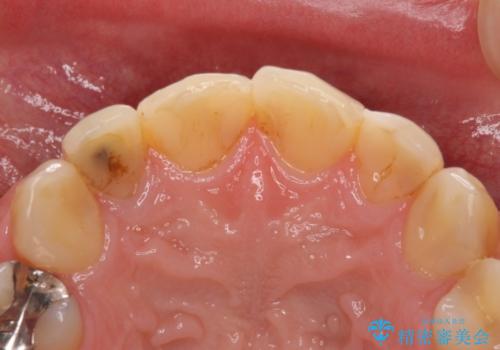

- 前歯の見た目を主訴にご来院された患者様です。虫歯治療を複数回繰り返して、前歯のつめものがつぎはぎになっていました。

患者様は前歯の見た目の改善を主訴にご来院されました。上の前歯6本とも古いつめものがつぎはぎになっていましたが、まずは1番目立つところを治すことをご希望でした。相談の結果、今回は2本できれいになるように工夫しました。

患者様には大変満足して頂きました。